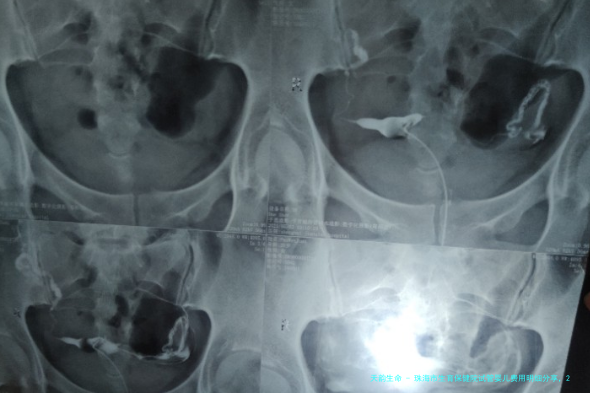

珠海市生育保健院全貌